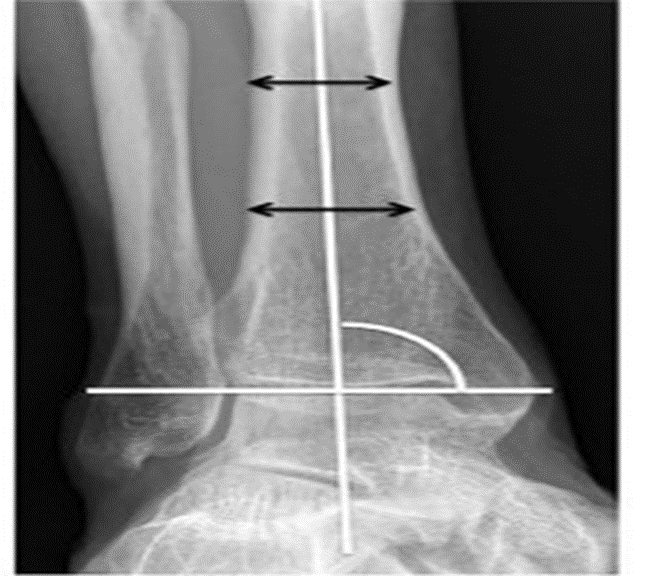

A complete clinical and neurological examination was done for all the patients. The signs and symptoms of local manifestation, such as pain, swelling, and restriction of motion were recorded. For all patients radiographs of Ankle Antero-posterior and lateral views were taken. X-ray Foot Antero-Posterior and lateral views were also taken for all patients to rule out associated Subtalar arthritis. The allocation of the type of fixation for the subject was done with double blinding. Radiologic outcomes were measured by: (1) Rate of union, (2) Rate of adjacent joint arthritis, (3) Alignment of the ankle joint. Functional outcomes were measured by using the AOFAS score (American Orthopedic Foot and Ankle Society score). Subjective assessments of the patients were done utilizing the Cumberland Ankle Instability Tool (CAIT). This evaluation was performed based on preoperative radiologic data and at postoperative clinical visits at 2 mo, 6 mo, and 12 mo required postoperatively. Ankle joint AP and lateral view X-rays taken while the patient was bearing weight were used to determine the ankle joint's alignment after surgery. In the AP projection, the angle between the tibia's long axis and a line parallel to the talus's long axis is found. In the lateral projection, the angle between the tibia's long axis and a line that is perpendicular to the talus’s long axis is measured. Digitalized X-rays and measurement instruments are used to identify the ankle joint's axis in the AP and lateral views. When more than five degrees of valgus or any amount of varus malalignment is observed at the ankle joint in the AP view, it is considered malalignment. The angles were measured using a protractor application.

In this study, the angle between the tibia's long axis and a line parallel to the talus's long axis is determined in AP projection. The mean angle was 89.6 degrees (85-100 degrees) in the intramedullary nailing group and 91.4 degrees in the corticocancellous screw group. The angle between the tibia's long axis and a line that is perpendicular to the talus's long axis is measured in lateral projection. The mean angle was 40.5 degrees (30-45 degrees) in the intramedullary nailing group and 41.6 degrees in the corticocancellous screw fixation group.

Picture 1: Shows the angle between the tibia's long axis and a line parallel to the talus's long axis